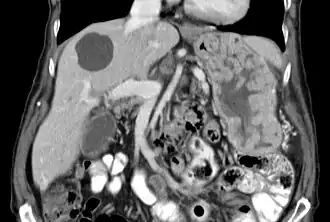

Bij het syndroom van Ménétrier wordt de maag gekenmerkt door grote, kronkelige maagplooien in de koepel van de maag (fundus gastricus) en het lichaam, waarbij het antrum (middelste deel van de maag) over het algemeen gespaard blijft, waardoor het slijmvlies een kasseien- of cerebriform (hersenachtig) uiterlijk krijgt.[4] Histologisch gezien is het meest karakteristieke kenmerk massieve foveolaire hyperplasie (hyperplasie van oppervlakte- en klierslijmcellen).[5] De klieren zijn langwerpig met een kurkentrekkerachtig uiterlijk en cystische verwijding komt vaak voor. De ontsteking is meestal slechts bescheiden, hoewel sommige gevallen duidelijke intra-epitheliale lymfocytose vertonen. Diffuse of vlekkerige klieratrofie, duidelijk als hypoplasie van pariëtale (exocrinocyti parietales) en hoofdcellen (exocrinocyti principales), is typisch.[3]

De grote plooien van de maag, zoals gezien bij het syndroom van Ménétrier, zijn gemakkelijk te detecteren door röntgenfoto's na een bariumpap (bariumsulfaat) of door endoscopische methoden. Endoscopie met diepe maagslijmvliesbiopsie (en cytologie) is vereist om de diagnose te stellen en andere aandoeningen uit te sluiten die zich op een vergelijkbare manier kunnen voordoen. Een niet-diagnostische biopsie kan leiden tot een chirurgisch verkregen biopsie van de volledige dikte om maligniteit uit te sluiten.[5] Cytomegalovirus (CMV) en Helicobacter pylori serologie moeten deel uitmaken van de evaluatie.